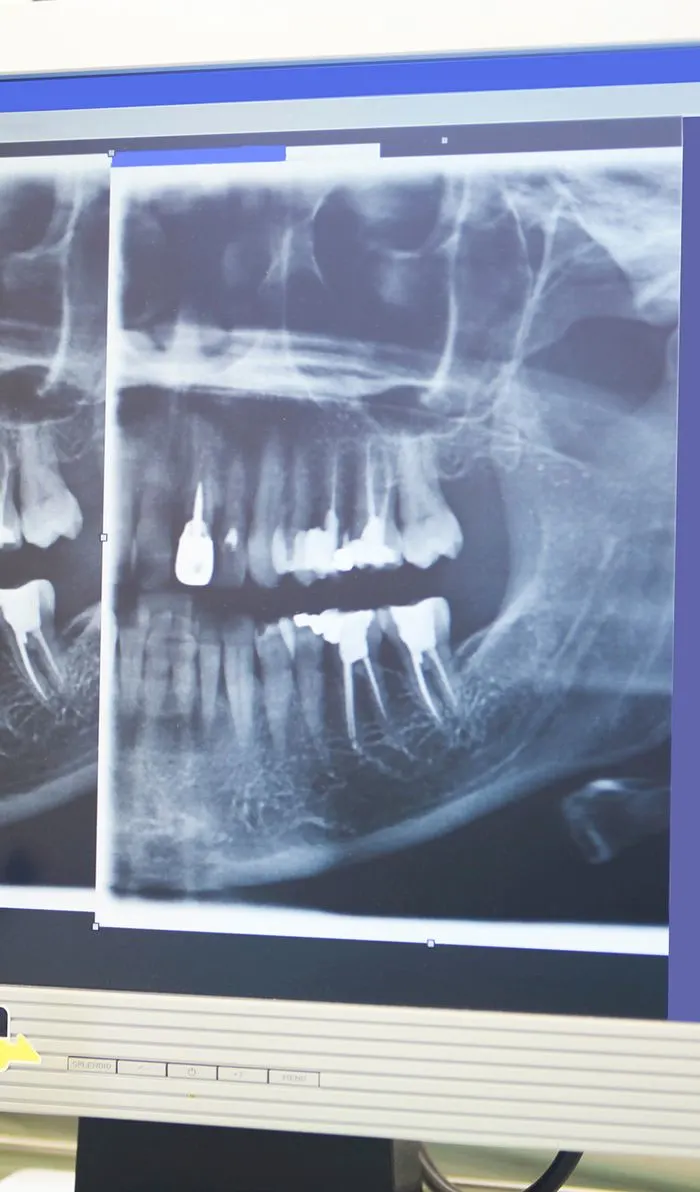

X-ray

Diagnostics & Preparation

Your dentist will begin with a comprehensive examination of your tooth and x-rays to identify the cause of your dental discomfort. If an infection is present, they'll assess its severity to determine if a root canal is the appropriate treatment option.If root canal therapy is necessary, your dentist will ensure the treatment area is completely numb, including the nerves. Before starting the procedure, they'll discuss various sedation options with you to ensure your comfort throughout the treatment.